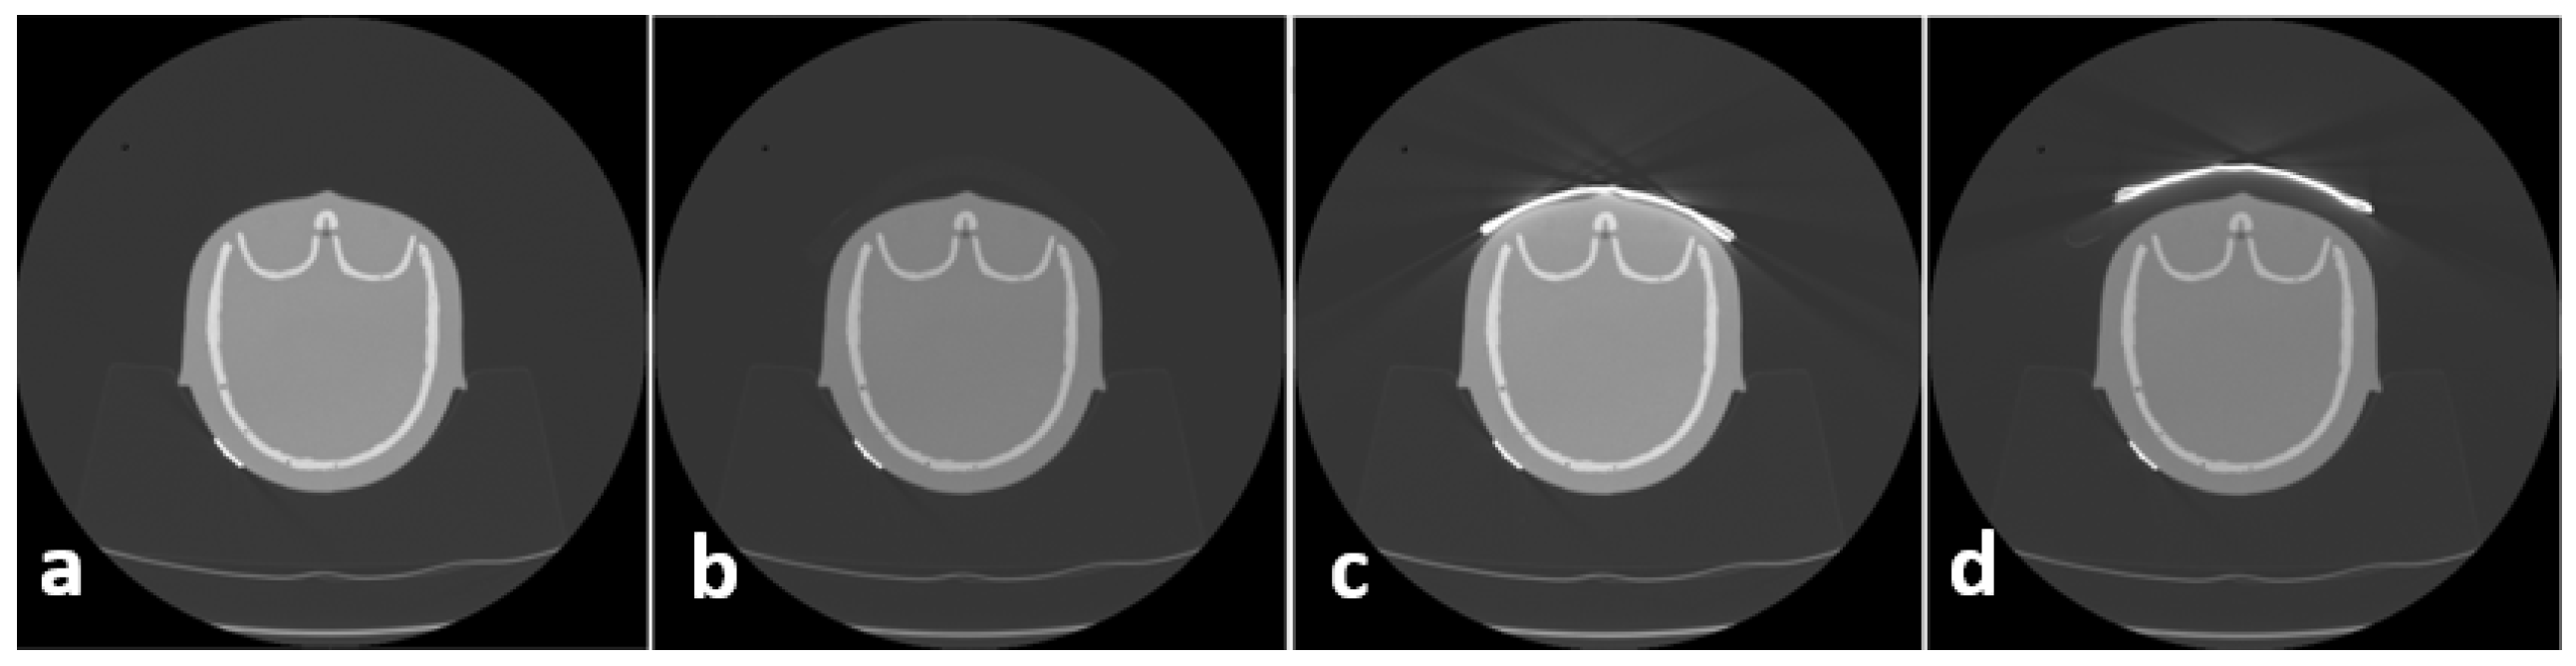

In order to overcome this disadvantage, the following approach proved to be successful at the authors’ institution: a 2.0 cm standoff foam is placed between the patient and BS to reduce artifacts in superficial areas. To assess the influence of BS as well as the influence of foam on image quality, CT scans were acquired in the following way: phantom alone, phantom + foam, phantom + BS, and phantom + foam + BS, as depicted in Figure 2. These scans were conducted only for the assessment of image quality; therefore, no dosimetric values were acquired.

Figure 2.

Protocol for quality assessment included 4 scans pro series: phantom (a), phantom + foam (b), phantom + bismuth shield (c), phantom + foam + bismuth shield (d).